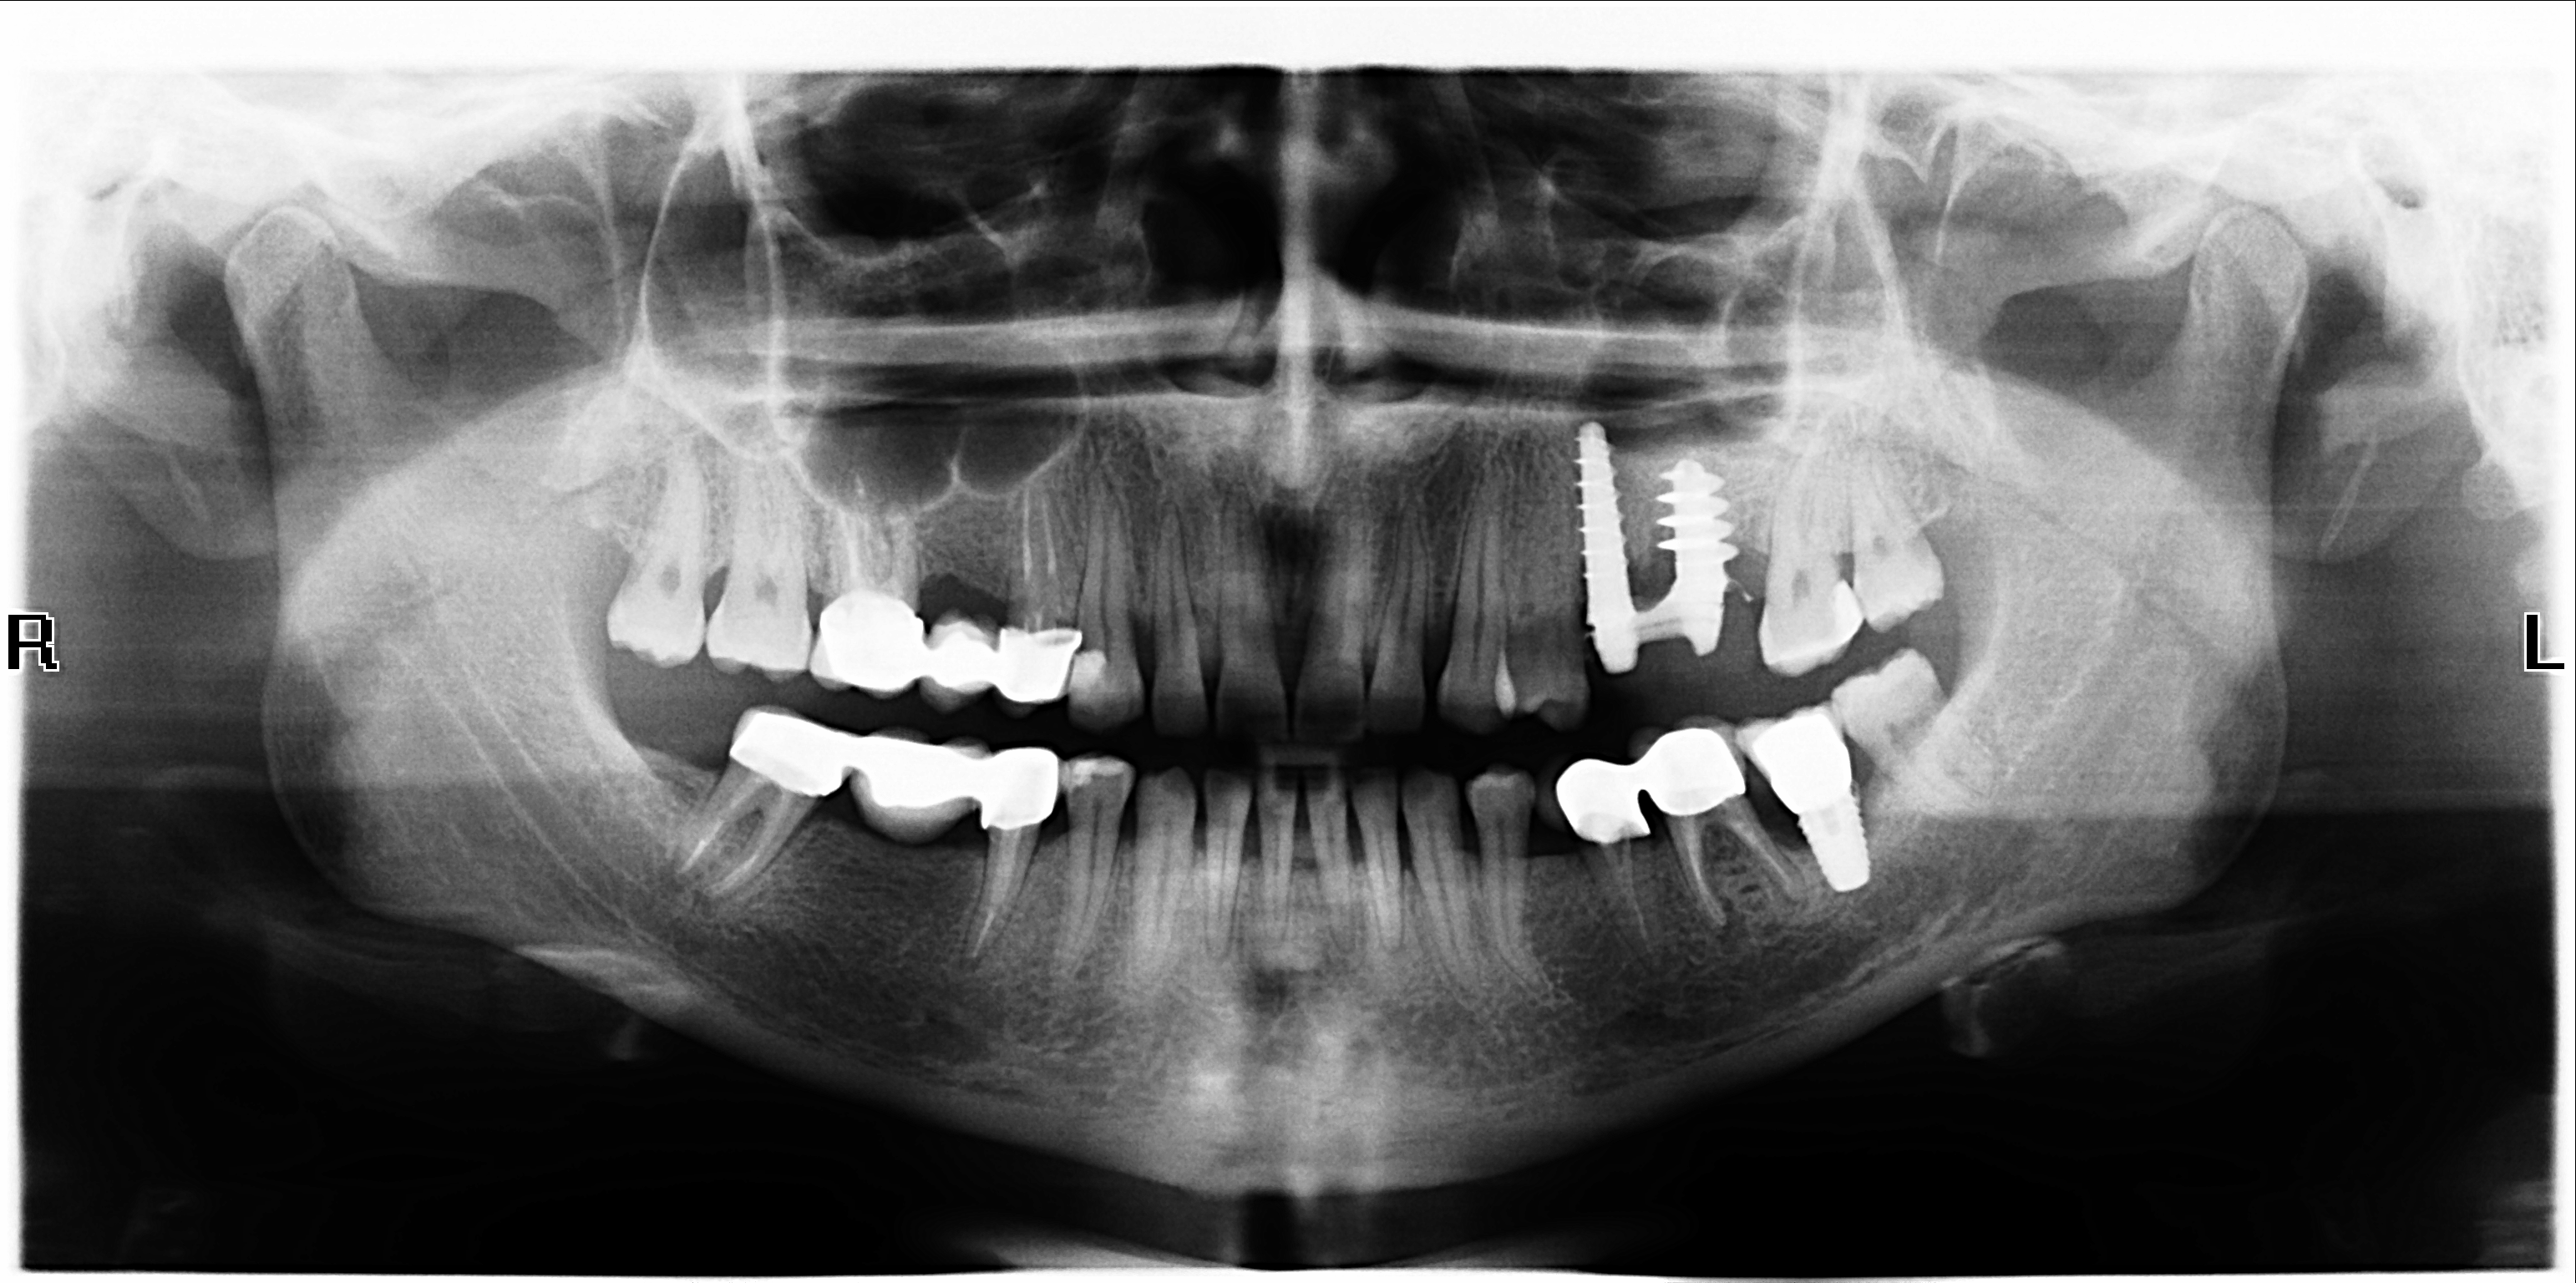

14.bmp